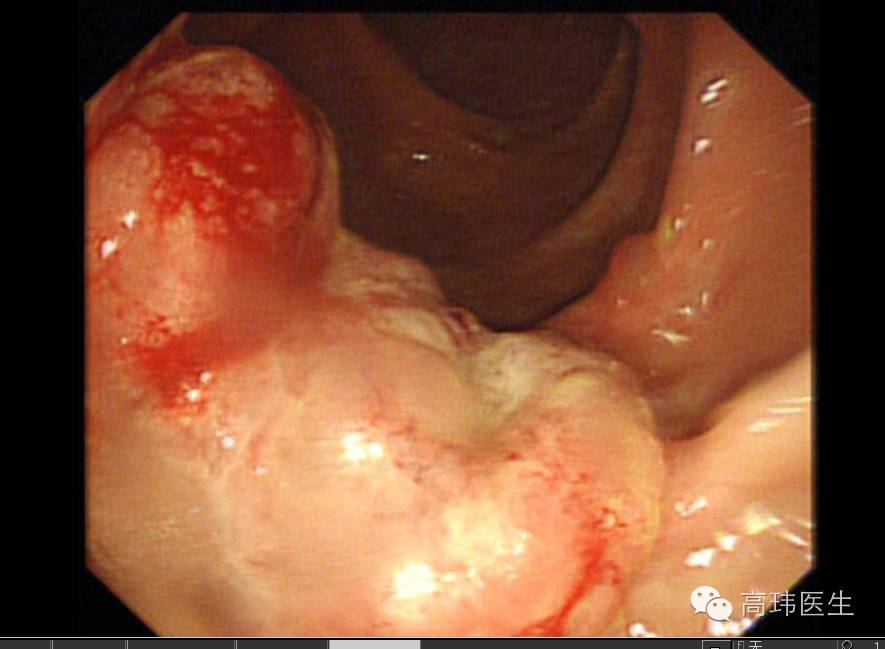

病例60岁女性患者,三年前在山东因结肠脾曲癌行姑息性左半结肠切除术,今3月因腹部不适查肠镜有发现升结肠近肝区、降结肠两处巨大溃疡性肿瘤,全腹增强CT显示结肠癌术后肿瘤复发并侵及邻近胃壁、空肠、胰腺及脾脏,肝右叶考虑转移瘤